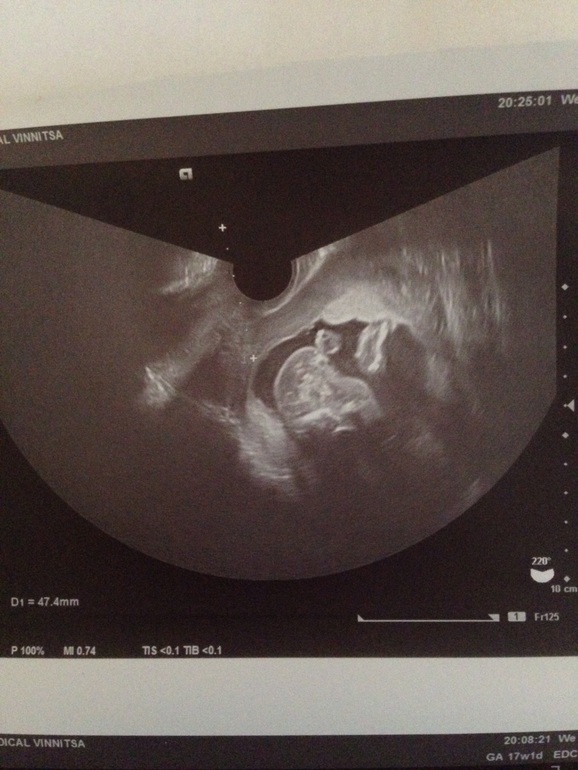

УЗИ, КТГ, доплерНе могу разобрать фетомеирию, срок 17-18 нед. Сказали всё ок, меня смущает диаметр живота, 34 см, окружность то вроде как норм 108 га 17 недель, а вот диамеир странно, по таблице как-то как на 13😱 Кто разбираеться в фетометрии??? Правда тут на ураинском. И ниже ещё фото непонятно чего ,там типа попа и видно пол, и что там я не пойму?)) как думаете кто там? У меня есть бумажка с написанным полом, ещё не смотрели🙈😀 потом расскажу вам угадали вы или нет😂

вот я тоже не понимаю, сказали на этом снимке типа видно.... Но я ничего не вижу , только пятна)

Я вижу голову, ручку, ножки, понимаю где попа, но абсолютно ничего не вижу в том месте где пол. Потому, может быть девочка🤷♀️